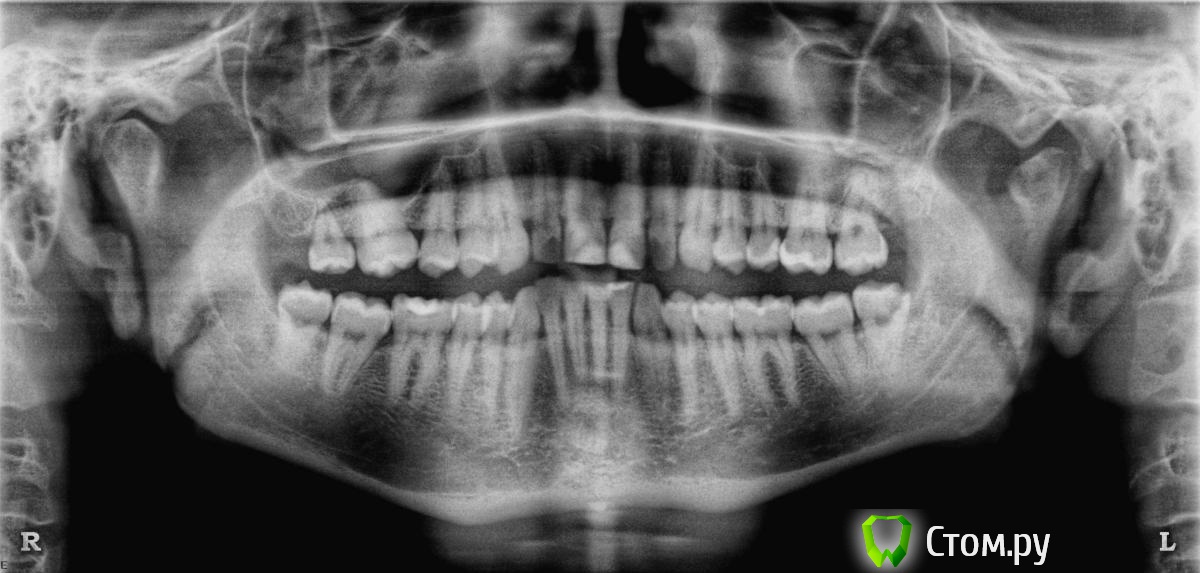

anvladd Опубликовано 5 февраля, 2014 Поделиться Опубликовано 5 февраля, 2014 иногда приходится спаивать при подвижности зубов. Но судя по вашему снимку у вас не так.Им так легче короче говоря. по какой причине коронуете? 1 Ссылка на комментарий

maxperevod Опубликовано 5 февраля, 2014 Автор Поделиться Опубликовано 5 февраля, 2014 Извиняюсь за неправильную терминологию. Ортопед.Да, зубы все живые. Фото только в таком ракурсе. Больше никак. Ссылка на комментарий

anvladd Опубликовано 5 февраля, 2014 Поделиться Опубликовано 5 февраля, 2014 Норм такие времяшки. 1 Ссылка на комментарий